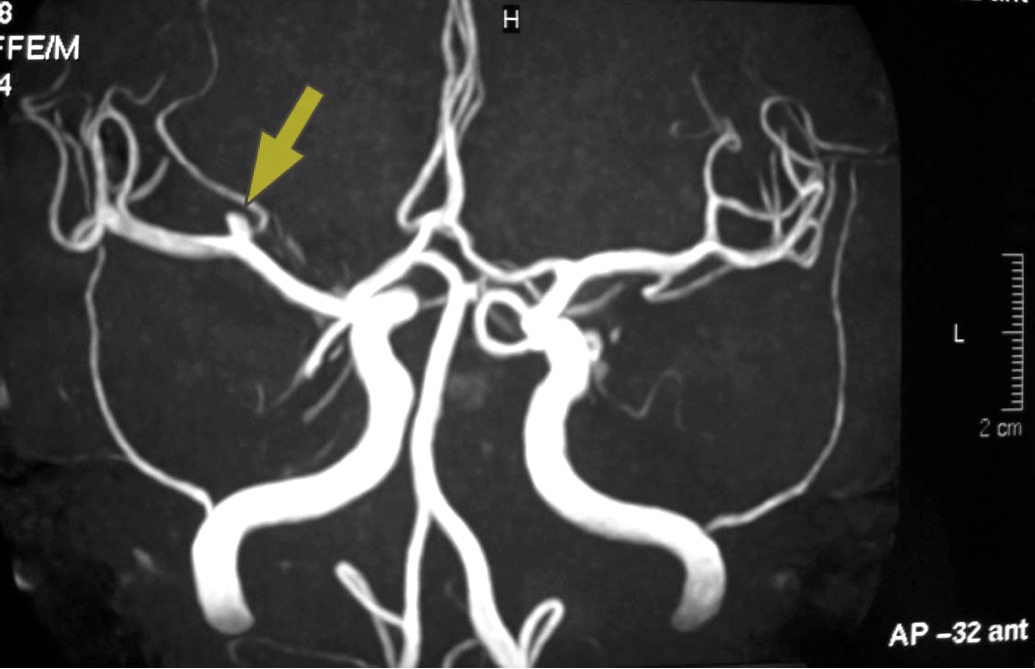

<未破裂右中大脳動脈瘤:約3mm MRA画像>

<上記MRAの3D画像(左右が反転してるのは後方から見ているから)>